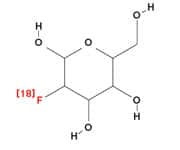

Limitations of PET ScansAs with all medical testing, PET/CT scan interpretation is associated with one of two kinds of statistical errors. They can result in a “false negative” result, incorrectly indicating absence of a tumor, when in fact a tumor is present. False negatives can occur when factors are present that limit how much FDG a tumor can take up from the blood.13 This may happen with blood vessel narrowing that reduces blood flow to the tumor, or when a tumor has grown so fast that many of its cells die off. Other contributing factors may include the unique cellular characteristics of the individual tumor. On the other hand, a “false positive” i.e., incorrectly indicating presence of malignant tissue when cancer is absent, can arise when non-malignant cells have increased glucose uptake or utilization. This may occur in certain infections and with many inflammatory processes. False positive readings are not uncommon following cancer surgery, when a patient has residual inflammatory tissue that is incorrectly read as persistence of tumor. This can be circumvented with additional acquisitions of the abnormal area on the PET study and a proper understanding of the biochemistry of malignant and non-malignant conditions. But there’s another type of error that is of serious concern to Dr. Black. It has nothing to do with the technology, and everything to do with how the PET/CT study is being interpreted, which in and of itself can produce either false negative or false positive results. The rapid expansion of PET technology has resulted in a large number of studies being read by physicians who simply haven’t been adequately trained. The issue is compounded by a lack of standardization in the way scans are read. Surprisingly, many PET/CT reports are simply narratives, which are lacking in standard categories and in quantifiable numerical values. Furthermore, many inexperienced readers fail to routinely correct the quantitative degree of uptake in the area of abnormality that is detected by the scanner. The uptake defined on the scan will vary considerably depending upon the elapsed time from when the radiotracer was injected into the patient. There are other issues as well, including the patient’s body weight and the proper calibration of the PET scanner itself.17 Without addressing such issues, Black comments, it is nearly impossible to accurately monitor response to therapy, or to determine real progression of disease, and these are two of PET scanning’s most potentially valuable contributions. Even simply detecting a real tumor is much more difficult without a standardized, corrected reading. Since PET/CT scans do expose patients to radiation, Dr. Black believes that every scan should yield the maximum amount of information. “Too often,” he says, “Physicians reading these scans describe findings without insight or provision of clinically useful and applicable information.” Often times the reports are essentially a discourse on the anatomic findings obtained from the CT portion of the study with little emphasis placed on the information delineated on the PET component of the examination. In the space remaining, we’ll demonstrate how Dr. Black approaches the interpretation of PET scans with an eye towards providing that insight in a way that helps physicians, and ultimately patients, optimally manage the challenges of cancer care.